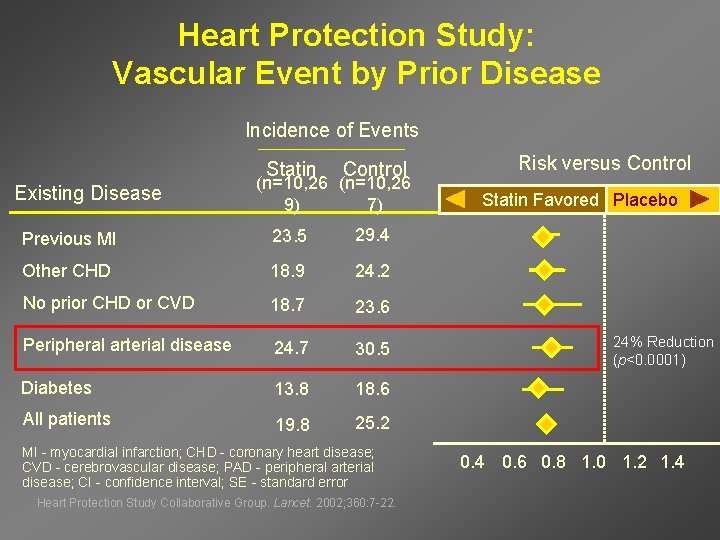

Heart Protection Study: Vascular Event by Prior Disease Incidence of Events Statin Existing Disease Control (n=10, 26 9) 7) Previous MI 23. 5 29. 4 Other CHD 18. 9 24. 2 No prior CHD or CVD 18. 7 23. 6 Peripheral arterial disease 24. 7 30. 5 Diabetes 13. 8 18. 6 All patients 19. 8 25. 2 MI - myocardial infarction; CHD - coronary heart disease; CVD - cerebrovascular disease; PAD - peripheral arterial disease; CI - confidence interval; SE - standard error Heart Protection Study Collaborative Group. Lancet. 2002; 360: 7 -22. Risk versus Control Statin Favored Placebo 24% Reduction (p<0. 0001) 0. 4 0. 6 0. 8 1. 0 1. 2 1. 4